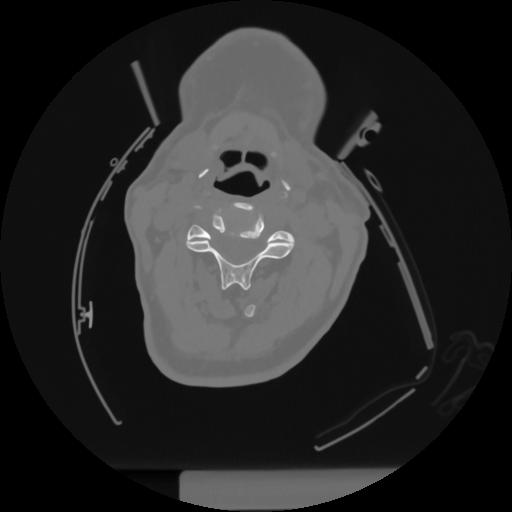

12 P.BLANDAS,,Vol,0.5,P.BLANDAS,,